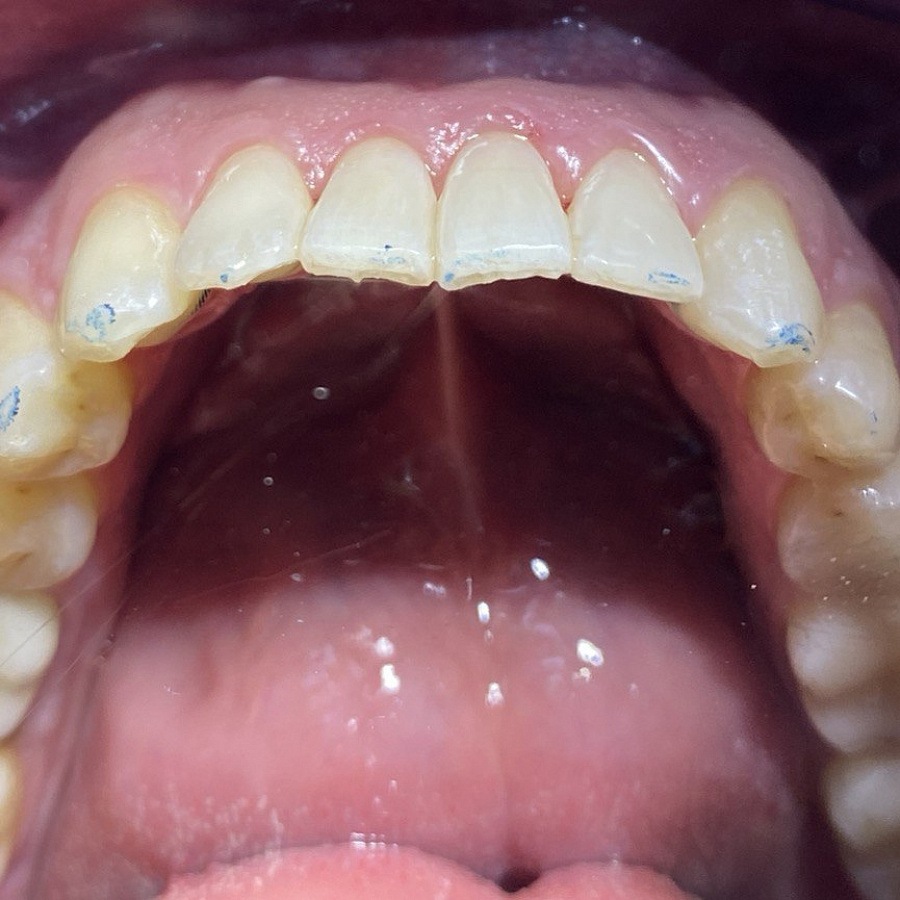

- ортодонтическое лечение с помощью элайнеров

Ортодонтическое лечение с помощью элайнеров длилось 10 месяцев. Далее последовало протезирование и установка виниров.